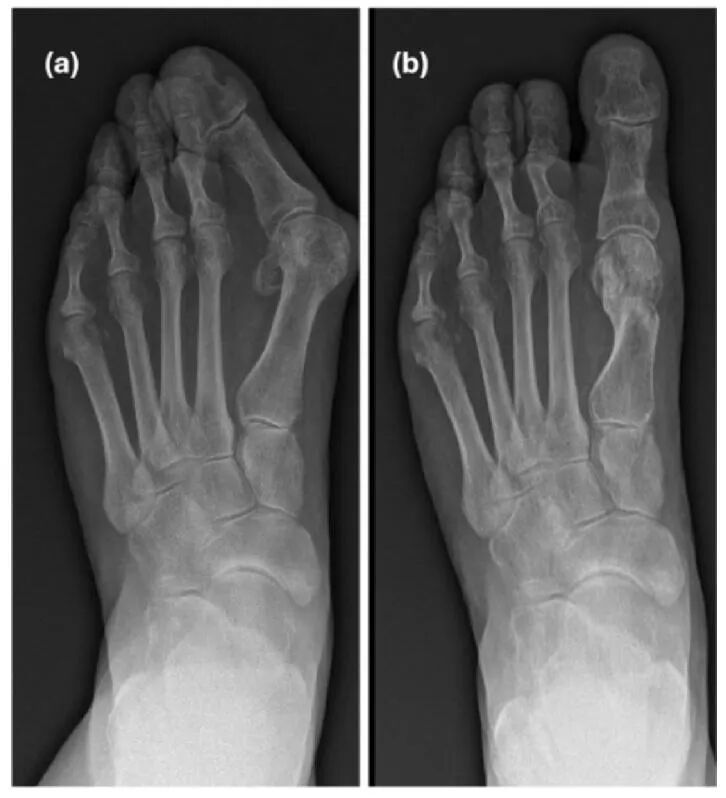

拇外翻是一种常见的、复杂的、进行性的前足畸形,具有多种临床症状和多因素病因。矫正拇外翻畸形的理想手术治疗方案仍存在争议。已有多种带或不带软组织松解的开放性骨性手术被描述,包括第一跖骨截骨术、第一跖趾关节(MTPJ)融合术或跖楔关节(MTCJ)融合术。在过去十年中,微创手术(MIS)因其临床和放射学结果与传统开放手术相当而越来越受欢迎。

不同代际的微创技术代表了技术和手术方法的进步。Reverdin截骨术是第一代拇外翻微创手术,涉及第一跖骨头的关节内内侧闭合楔形截骨术,无需内固定。第二代技术最初由Bosch描述,采用囊外截骨手术,并通过轴向克氏针固定。第三代技术对该技术进行了改进,使用螺钉进行固定。越来越多的科学证据表明,第三代拇外翻微创手术包括远端跖骨截骨内固定,与第一代和第二代相比,能提供更准确和稳定的矫正。

无螺钉微创三平面截骨术在60岁及以上患者的拇外翻治疗中,在临床、功能和放射学方面均有显著改善。